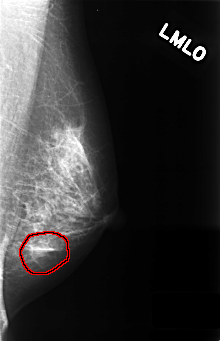

C_0385_1.LEFT_MLO

LEFT_MLO LINES 4432 PIXELS_PER_LINE 2856 BITS_PER_PIXEL 12 RESOLUTION 50 OVERLAY

FILE: C_0385_1.LEFT_MLO.OVERLAY

TOTAL_ABNORMALITIES 1

ABNORMALITY 1

LESION_TYPE MASS SHAPE OVAL MARGINS ILL_DEFINED

ASSESSMENT 4

SUBTLETY 4

PATHOLOGY BENIGN

TOTAL_OUTLINES 1

BOUNDARY